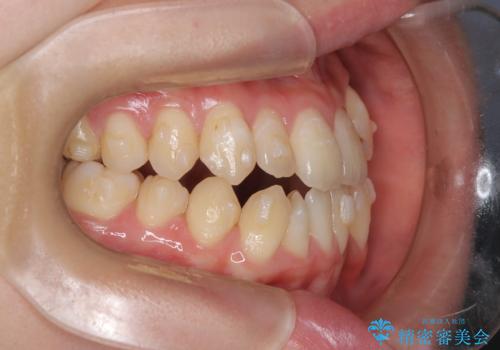

診査の結果、すでに下顎前歯の抜歯が行われていましたが、マウスピースの適合が著しく悪くなっており、歯が計画通りに動いていない状態でした。また、歯を支える骨の厚みや歯肉の薄さを考慮すると、このままマウスピースによる傾斜移動を続けるのは歯肉退縮(歯茎が下がること)のリスクが非常に高いと判断。

装置の変更と歯肉への配慮: ワイヤー矯正は歯の根(歯根)を平行に移動させる「歯体移動」を得意としています。本症例では、歯肉退縮を防ぐために、歯の傾きを精密にコントロールしながら抜歯スペースを閉じる必要がありました。ワイヤー装置を用いることで、インビザラインでは難しくなっていた三次元的な細かい調整を可能にしました。